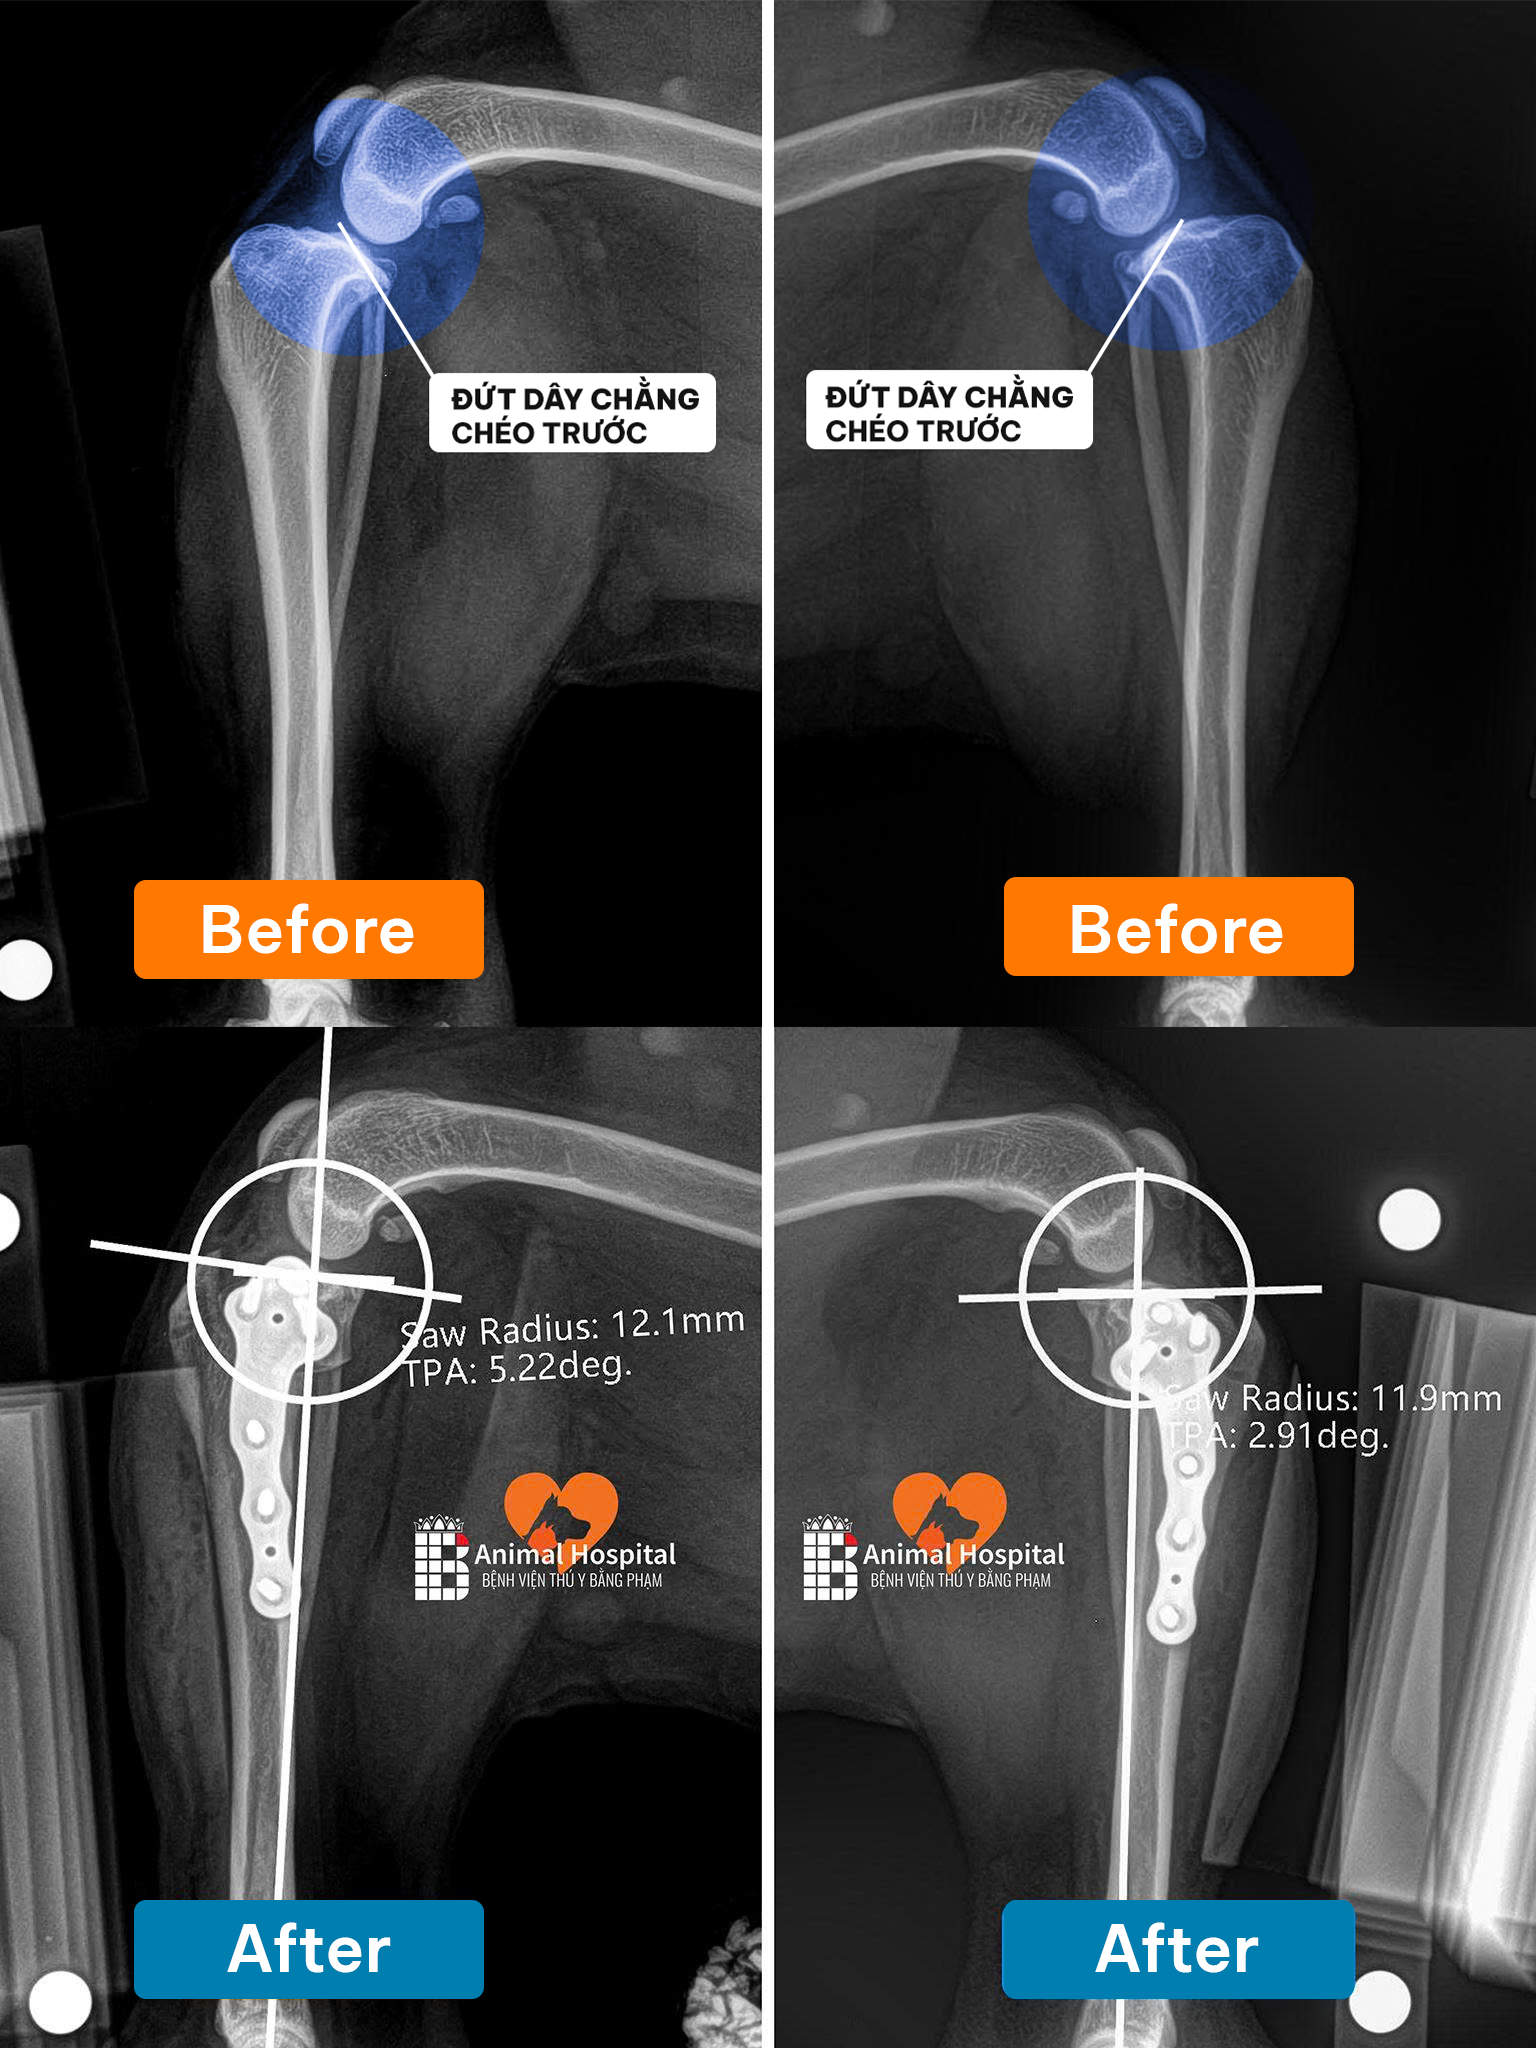

- Khi cần lập kế hoạch phẫu thuật hoặc đánh giá trước và sau điều trị – CT cung cấp ảnh 3D và thông tin rõ nét về vị trí, kích thước và mối quan hệ của tổn thương.

🔍7. Hình Ảnh Thực Tế – Kết Quả Sau Khi Chụp

Hình ảnh CT thể hiện chi tiết từng lớp cấu trúc trong cơ thể, giúp bác sĩ:

- Xác định chính xác vị trí khối u, ổ áp xe, hoặc chấn thương sâu.

- Lên kế hoạch phẫu thuật hoặc điều trị nội khoa chính xác.